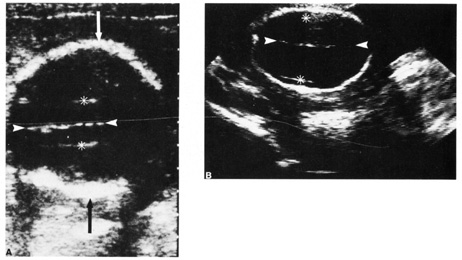

A second trimester ultrasound is usually done at 20 to 22 weeks' gestational age. The most commonly used fetal measurements are biparietal diameter, length of the femur or other long bones, and abdominal and head circumference. In addition to measurements, an anatomic survey is also done to evaluate the fetal brain (Fig. 9), spine, stomach, heart, kidneys, placental location and assessment of amniotic fluid (Fig. 10). If maternal risk factors are present, tetra screening results are abnormal, or there are abnormal findings on the anatomic survey, the patient is sent for a comprehensive ultrasound. The components of a comprehensive ultrasound are shown in Table 9. The ultrasound findings associated with Down syndrome include cardiac defects or enlargement, cystic hygroma (Fig. 11), duodenal atresia (Fig. 12), omphalocele, polyhydramnios, choroids plexus cyst, and renal calyceal dilation.

Fig. 11. Early second trimester ultrasound showing posterior neck cystic mass consistent with cystic hygroma. Image courtesy of GE Medical Systems.

Fig. 12. Duodenal atresia in a second trimester fetus. A: Ultrasound scan of fetal abdomen (arrowheads) showing two fluid-filled structures (arrows). Increased amniotic fluid (polyhydramnios) surrounds the fetus. B: Newborn radiograph of upper abdomen demonstrating gas-filled stomach (S) and duodenum (D), which are typical findings of duodenal atresia. (Courtesy of Alfred B. Kurtz, MD)